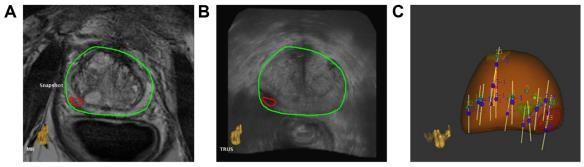

ThissectiondiscussesanewPCaimagingmethodthatcombinesUSandMRI.Fusionimagingcombinesthe advantagesof USandMRimagingwithoutcompromisingtheirdiagnosticclinicalrelevance.mpMRI'sclinicallysubstantialPCadetection sensitivityandspecificityhavetransformedPCadiagnosis.Hambrocketal.comparedin-borempMRI-guidedbiopsiesto10coresystematicTRUSbiopsiesinmenbeforeRP.MRI-guidedbiopsiesdetectedPCa88%betterthangrayscaleTGBs(55%;Pvalue 0.001). MRI is accurate, but given the number of prostate biopsies conducted each year, it is too expensive and impracticaltoutilizealone(approximatelyamillionintheUSalone).In-borebiopsiestakelongerwithoutreal-timeimaging, makingpatientsuncomfortable.Duetotheintense magneticfield,safetyrequiresspecialistequipmentandneedles.In-bore biopsieswithreal-timeimagingandfasterroboticneedleplacementsarebeingdeveloped.[26-27]GrayscaleUSimagingis cheaper and faster than in-bore MRI, although it may not be as diagnostic. mpMRI–USfusion-guided biopsies are now a feasible alternativetoMRI- guided, inbore, and conventional TGBs. MRI–US fusion-guided biopsies are conducted in an outpatient clinicwith liveB-modeUS,reducing expenses and treatment time.Toidentifyaberrant MRI areas,thepatient undergoesanmpMRIpelvicexaminationbeforetheoperation.Thebiopsyproceduretargetsthesesitesbymappingthemonto USimagesviaimagefusionorregistration.ExperturoradiologistscancognitivelyorvisuallyfuseMRIandUSpictures.Thisis subjective and may require knowledge only found in huge academic research institutions. Regulatory- cleared, commerciallyavailableMRI–USfusiondevicesaregrowingmorepopular.Real-timeUSbiopsiesofvirtual MRI targets are easier with fusion platforms. The platforms differ in US capture (3D volumetric, 2D sweep, etc.),biopsy targeting (e.g., electromagneticandelectromechanical),biopsyroute(transrectalvs.transperineal),and imagefusiontechnique(rigidvs. elastic).Mostsystems storebiopsied sites withabnormalgradinganduseMRI/US fusion-based targeting guidance.Active surveillanceandtargetedtherapydependonaccuratebiopsyplacements;therefore,thishasmajorimplicationsforpatients. Three widely investigated fusion biopsy platforms Artemis (Eigen), UroNav (Invivo/Philips), and Urostation will be discussed here(Koelis).BiopSee,VirtualNavigator,HI RVS,BioJet,MonaLisa,andLOGIQ9(MedCom,Esaote,Hitachi, and GeoScan)areotherplatforms(GEHealthcare).

Artemis. Eigen,USA,makesArtemis.SemiroboticmechanicalstabilityoftheTRUSprobeduringbiopsyreducesfree-hand distortion. ProFuse radiology software annotates worrisome lesions in 3D mpMR images before the surgery.The TRUS probemechanicallyrotatestoacquire3DvolumetricUSdata.This3DUSvolumeisrigidlyandelasticallymergedwiththe3D MRI volume(Fig.5A and 5B).Rigid fusioncorrects orientationvariations between 3D MRI and 3D US volumes, while elastic fusion accounts for local shape deformations caused by patientorientation,bladder/rectalfilling,andendorectal coilorTRUSprobepressure.FusiontransfersvirtualMRIlesion sitestoreal-timeTRUSimagesfortargeting.Afterfusion,a visiblegraphicalinterfacebasedonelectromechanical tracking and shot sites moves the probe/needle guide assembly to lesion spots (Fig. 5C). MRI–US fusion-based targeting and automatic template distribution of systematic, random biopsy cores based on prostate formand volumeareavailable. The Artemis system revealedcancer in53%of a mixedgroupof 171 men on active surveillance and earlier negative biopsies in a Sonn et al. investigation. Fusion biopsy-guided cores detectedthree timesmore malignancythansystematic randombiopsiesand more clinicallyrelevanttumors(P = 0.001). ThebiopsyfindingscorrespondedwithmpMRIsuspicionlevelofthetargetedlesions,andmenwiththehighest suspicion level had a 94% cancer detection rate. [28] Sonn et al. revealed 34% of prior negative men got PCa, 72% of whom had clinically severe illness. Fusion biopsies found 1.4 times but 15% as many unimportant tumors, accordingtoSonnetal. Wysocketal.comparedArtemis-targetedandexpertcognitivefusionbiopsiesin125menwith172MRI-suspiciouslesions. Artemistargetedfusionbiopsiesfound20.3%clinicallysignificanttumorspertargetcomparedto15.1%utilizingcognitive targeting(P=0.0523).Device-targetedbiopsywasmorepathologicallyinformativethancognitivebiopsies(P=0.0104).

UroNav. Invivo/PhilipsmarketstheUroNavplatform,createdattheNationalInstitutesofHealth,Bethesda,USA.Anexternal electromagneticfieldgeneratortracks andguidesneedlebiopsies transrectally. DynaCADforProstate marks problematic lesions on preprocessed 3D mpMR images. A 2D freehand sweep from prostate base to apexacquiresthe3DUSvolume duringbiopsy.A stiffmethodthataccounts forrotationalandtranslationalvariancescan fuse3D MRIand 3D US pictures. VisuallyadjustingtheUSprobepressureontheprostatecanchangethedistortionbetweentheUSandMR3Dpictures.After fusion,electromagneticguidanceguidestheprobe/needleassemblytovirtualMRIlesions.Pintoetal.discoveredPCain28%, 69%, and 90% of 101 patients using the UroNav platform (P< 0.0001). In their investigation, the number of mpMRI sequences (T2WI, DCE, DWI, and MRSI) that detected a lesion as positive low (2 or less), moderate (3), or high (4) determined its suspicion grade and the chance of canceruponbiopsy.Vourgantietal.foundPCain37%of195menwith priornegativebiopsies,and fusion-guided biopsies found high-grade malignancy in all males (n = 21), while systematic biopsies missed them in 12 individuals.[29] Siddiqui et al.discovered that targeted biopsy revealed 30%morehigh-risk cancer (P < 0.001) and 17% fewer low-risk cancer (P< 0.001). Targeted biopsies outperformed systematic biopsies in predictinglow-riskcancerin170menfollowingRP(P<0.05).

Urostation. Koelis, France's Urostation platform uses software image registration instead of electromechanical or electromagnetic tracking like Artemis and UroNav. A 3D US probe stitches together an initial volume. This 3D volume marksconsecutivebiopsyspots.TheUSvolumeiselasticallymergedwith3DMRimagestomapMRIlesions.Then,theUS probeisfreehand-manoeuvredtothelesionareasforbiopsy.A3Dvolumeistakenwiththeneedleinplaceandelastically fused with the initial 3D reference volume to confirm each biopsy location. Using fusion-guided biopsy, Ukimura et al. targeted MR-visible, hypoechoic, and isoechoic lesions on a phantom withthe Urostation platform.84% offusion-guided biopsieshitlesions.Inaretrospectiveinvestigationof90patients,Rud et al found PCa diagnosis rates of 10%, 27%, and 91%forlow-,medium-,andhigh-MRIsuspicionlevels.Fusionbiopsiesdetectedmoreclinicallyseriouscancerin152men thansystematicbiopsies(P=0.03).